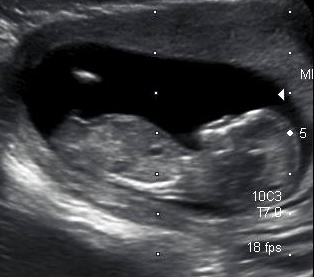

I was hoping that someone here could please guess the gender of my bambino!

The ultrasounds was done at 12 weeks + 2/3 days.